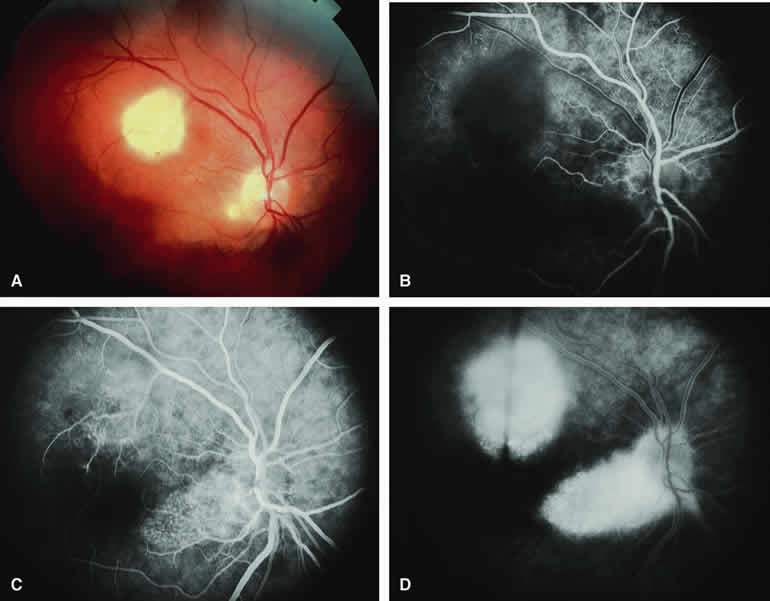

Typical Melanotic Choroidal Nevus

Fluorescein angiography of a typical choroidal nevus with bland surface features (see Fig. 1) shows the entire lesion to be hypofluorescent relative to the adjacent uninvolved choroid throughout the study. No large-caliber choroidal blood vessels are usually identifiable within the lesion. The retinal vasculature overlying the lesion appears well defined and normal on fluorescein angiography.

ICG angiography of a typical melanotic choroidal nevus (see Fig. 2) shows better definition of the basal area of the lesion than does fluorescein angiography. The entire lesion appears completely and uniformly dark throughout the ICG angiogram. Only the larger retinal blood vessels overlying the nevus are usually demonstrated on ICG angiography.